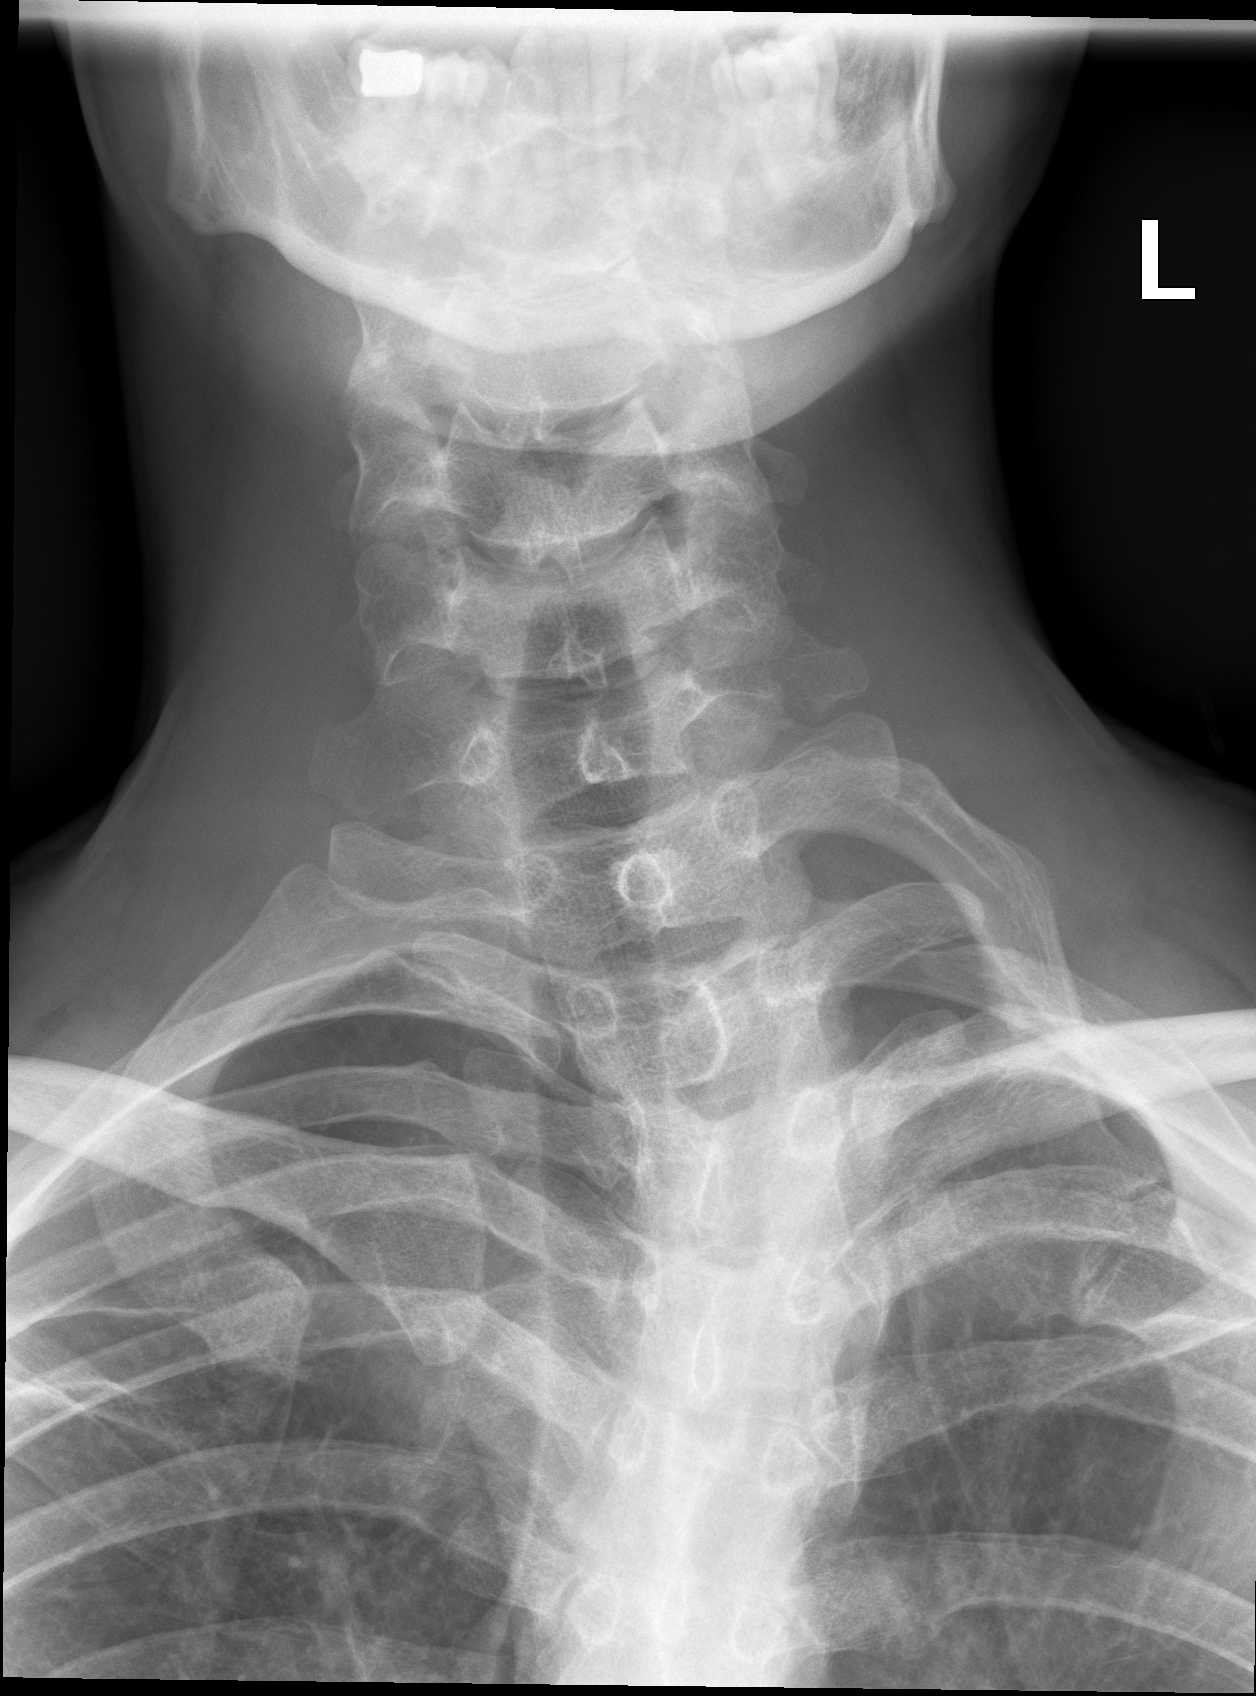

Медицина и диагностика: Аномалии ребер на рентгене